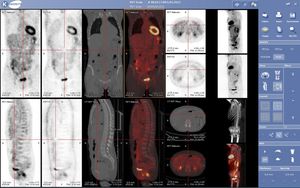

양전자 방출 단층촬영(PET)은 붕괴 시 양전자를 방출하는 방사성 동위원소를 이용하여 체내 물질대사를 추적하는 영상 기술이다. 방출된 양전자는 전자와 쌍소멸하여 감마선을 생성하며, PET 장비는 이 감마선을 감지하여 입체 영상을 재구성한다. 종양학, 신경 영상, 심장학 등 다양한 분야에서 활용되며, 플루오로데옥시글루코스(FDG)가 가장 일반적으로 사용되는 방사성 추적자이다. PET는 CT 또는 MRI와 결합하여 해부학적 정보와 대사 정보를 함께 얻는 PET-CT, PET-MRI 형태로도 사용된다. 비침습적이지만 전리 방사선 노출을 수반하며, 사이클로트론과 방사성의약품 생산 시설의 비용이 높다는 제한이 있다. 한국은 PET 장비 보급률이 높고, 건강보험 급여 확대를 통해 접근성을 높이고 있으며, 기술 수준 또한 세계적이다.

그 외 PET의 다양한 응용 분야는 다음과 같다.4. 1. 종양학

플루오로데옥시글루코스(FDG)를 이용한 PET 스캔은 임상 종양학에서 암의 진단, 병기 설정, 치료 반응 평가에 널리 사용된다.[4] FDG는 포도당과 유사한 물질로, 포도당 대사가 활발한 암세포에 많이 축적되는 성질을 이용한다.[4] 이러한 FDG의 축적 정도를 영상화하여 암의 위치와 크기를 파악할 수 있다.

FDG-PET는 특히 호지킨 림프종,[6] 비호지킨 림프종,[7] 폐암[8][9][10] 등 다양한 암종에서 활용된다. 2020년 연구에 따르면, 호지킨 림프종 환자의 중간 PET 스캔에서 음성 결과가 나오면 더 높은 전체 생존율 및 무진행 생존율과 관련이 있다는 증거가 발견되었다.[11] 다만, 이 증거의 확실성은 생존율에 대해서는 보통, 무진행 생존율에 대해서는 매우 낮았다.[11]

PET-CT는 PET와 CT를 결합한 장비로, 해부학적 정보와 대사 정보를 함께 얻을 수 있어 유용하다. 최신 PET 스캐너는 고급 멀티 검출기 배열 CT 스캐너와 통합되어 제공되며(PET-CT), 동일한 세션에서 두 스캔을 순차적으로 수행할 수 있다. 환자는 위치를 변경하지 않아도 되므로 두 영상이 정확하게 등록되어, PET 영상의 이상 부위가 CT 영상의 해부학적 구조와 더욱 완벽하게 연관된다. 이는 움직이는 장기나 구조의 상세한 뷰를 보여주는 데 매우 유용하다.